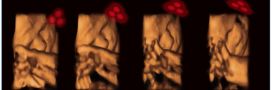

Babies’ preference for faces begins before birth

The visual development of babies in the womb has been explored for the first time ever, revealing a clear preference for face-like shapes.